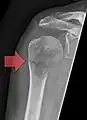

- Vues de fractures pathologiques

Fracture pathologique de l'humérus sur une métastase de carcinome du rein